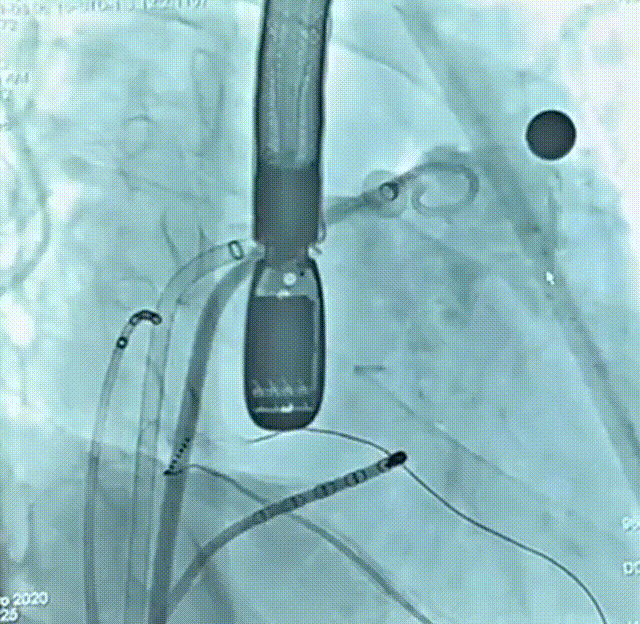

术前造影

患者为51岁男性,因“反复心悸7-8年”入院,有明确的脑梗死病史,近4年内出现2次脑梗死,右侧肢体存在活动障碍后遗症,考虑由房颤相关血栓栓塞造成。术前动态心电图示心律不齐,房颤律,心脏彩超示左右房内径增大、左室收缩功能减低;房颤CHA₂DS₂-VASc评分4分、HAS-BLED评分4分,血栓栓塞及出血风险均较高;食道超声联合CT重建示左房及心耳内未见明显血栓形成,左心耳偏大。结合评估结果和患者及家属意愿,拟使用我国自主研发的Bio-Lefort生物可降解左心耳封堵器,行导管消融+左心耳封堵“一站式”手术。射频消融完成后实施左心耳封堵,术中牵拉试验提示封堵器稳定,符合释放原则,整个封堵器释放过程一气呵成,术后造影显示无残余分流,术后超声证实封堵器位置良好,封堵结果十分理想,顺利完成手术。